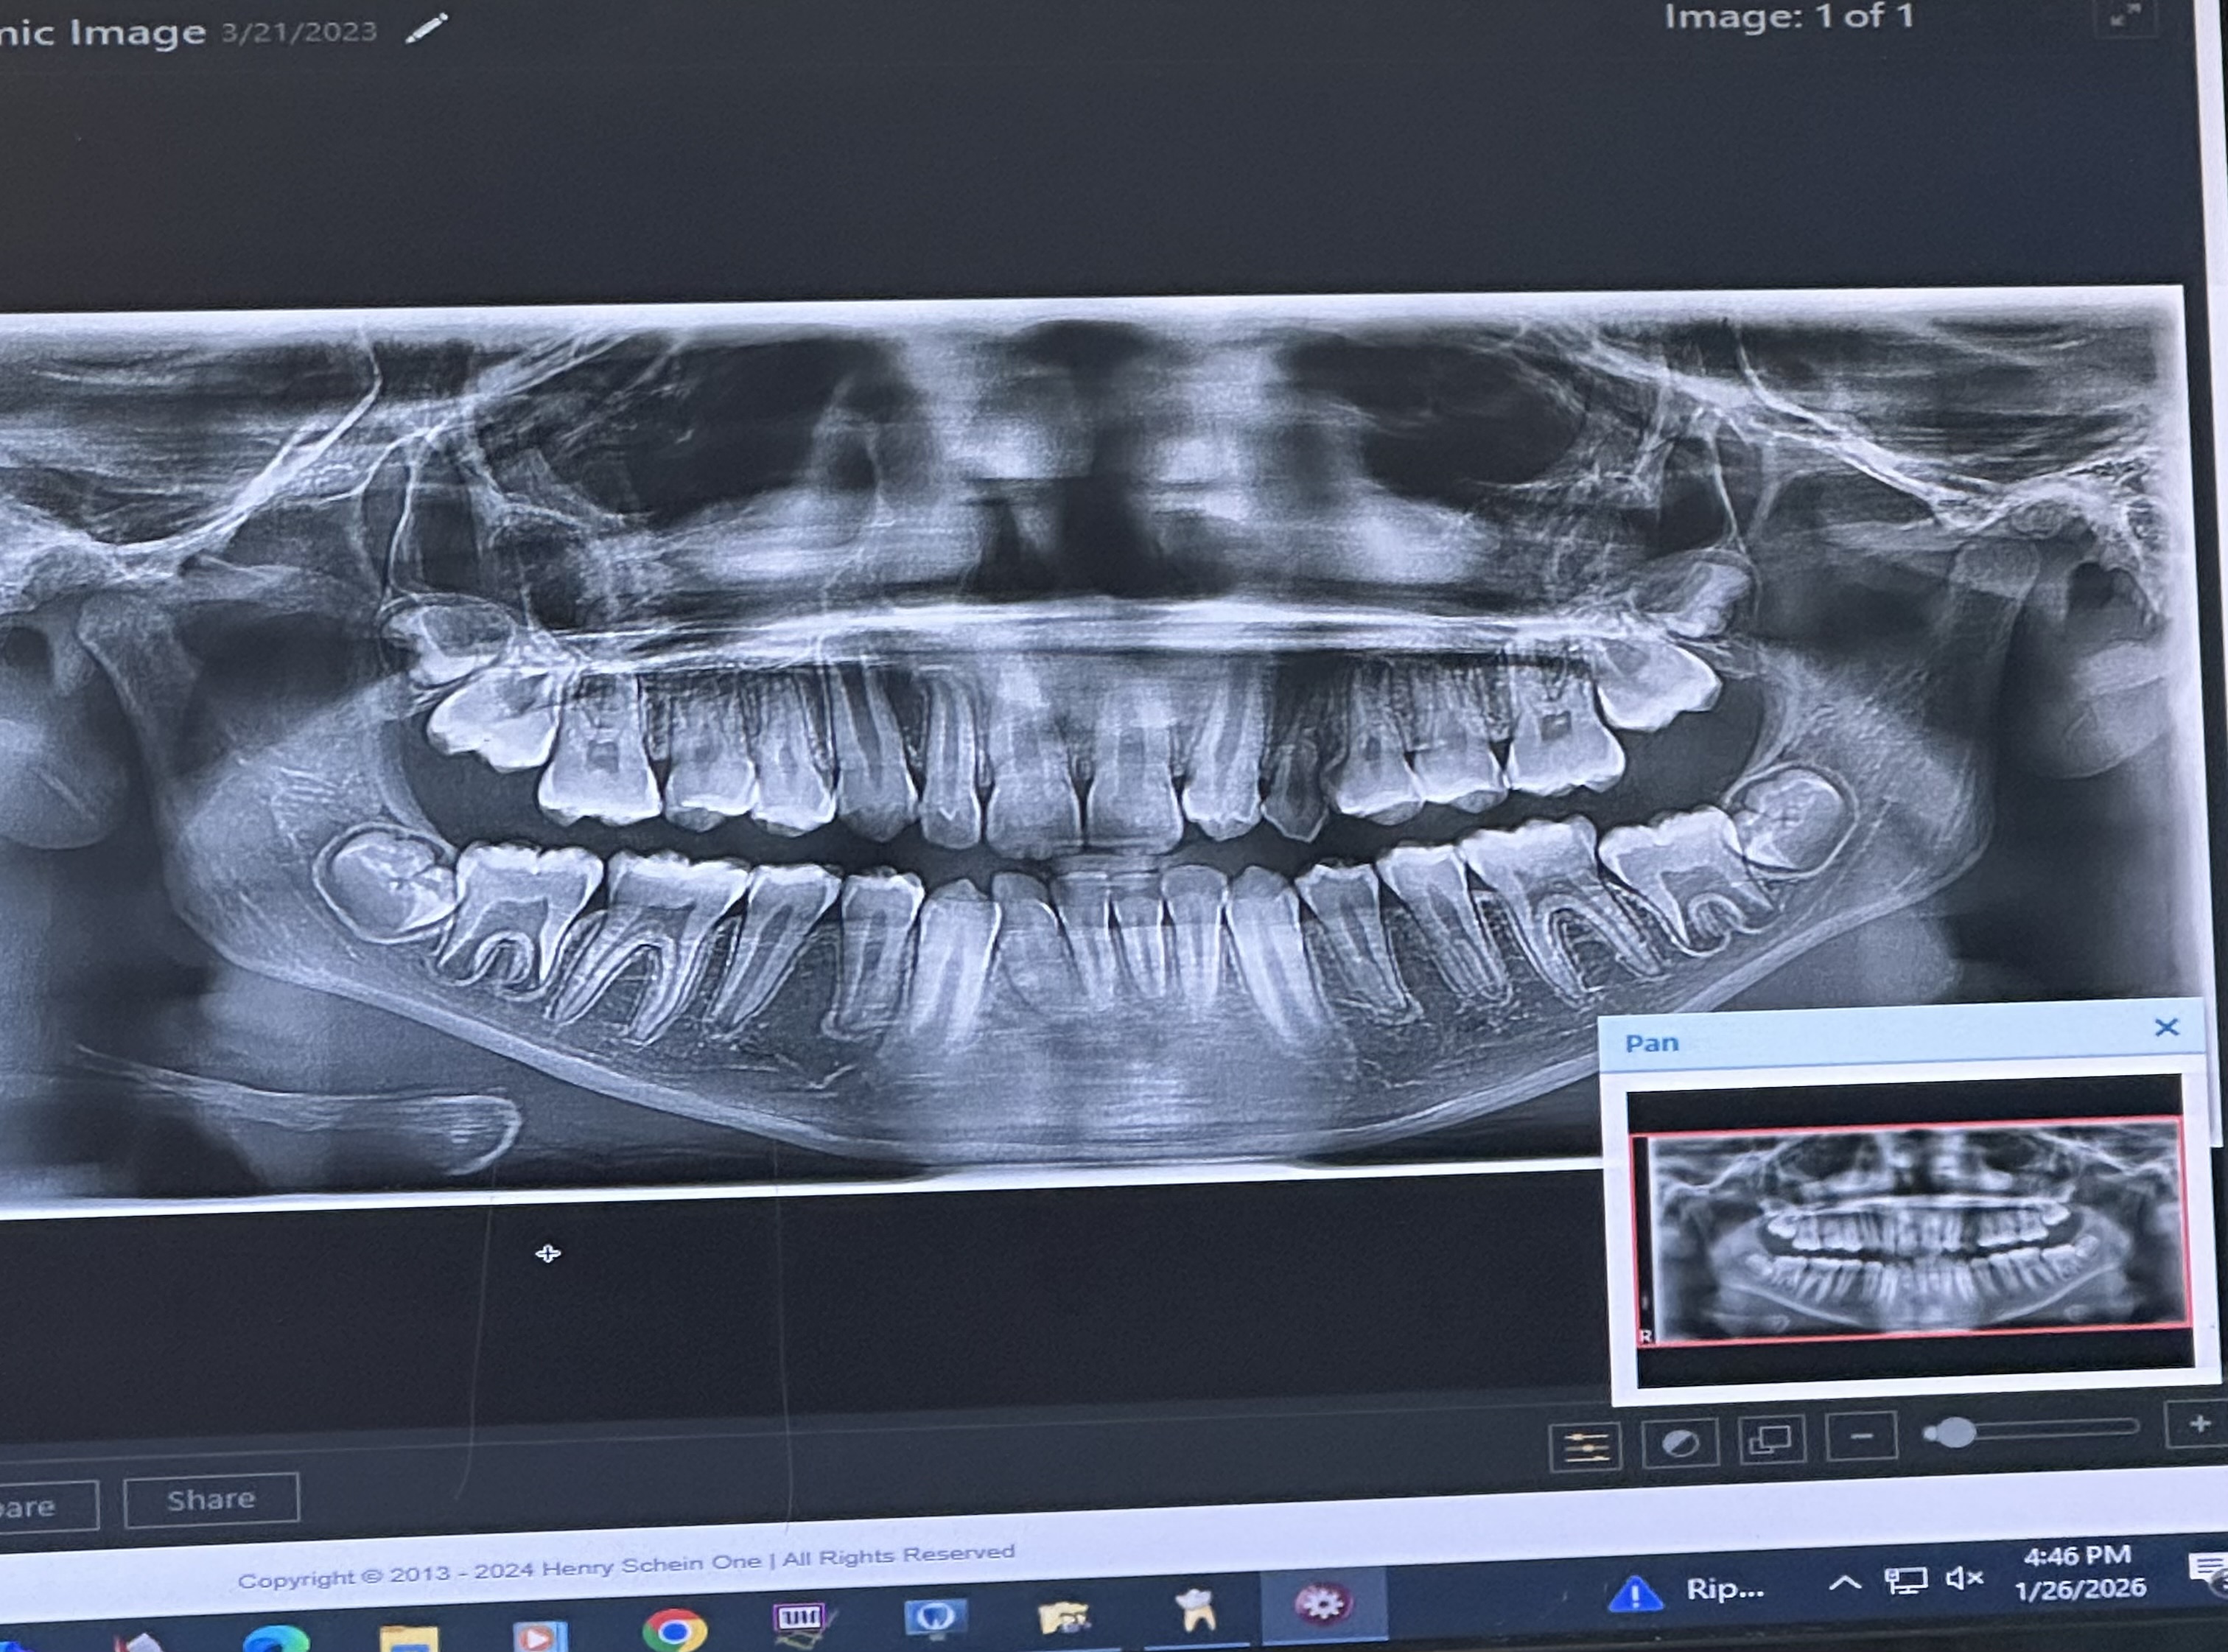

So Appearantly a tooth is stuck all the way in my nose that they have to lodge out but first I have to get a palate expander to make space for it m

I have tom cruise teeth basically I’m missing a incisor and my canine is temporary (baby tooth) while the rest of my teeth are permanent and the “missing” incisor is in my directly next to or like below my nasal area